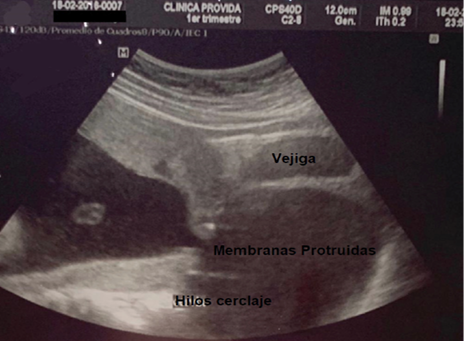

G1: aborto a las 20 semanas de gestación. G2: aborto a las 20 semanas de gestación. G3: aborto a las 21 semanas de gestación a pesar de haberse realizado cerclaje vaginal técnica McDonald a las 12 semanas por el servicio de ginecología-obstetricia del Hospital Básico Provida; se observa en la Figura 3 los hilos del cerclaje con la protrusión de membranas ovulares en vagina el día del aborto. G4: actual, edad gestacional 13 semanas por fecha de ultima menstruación (FUM).

Figura 3. Membranas protruidas en vagina

Fuente: Servicio de Ginecología-Obstetricia, Hospital PROVIDA